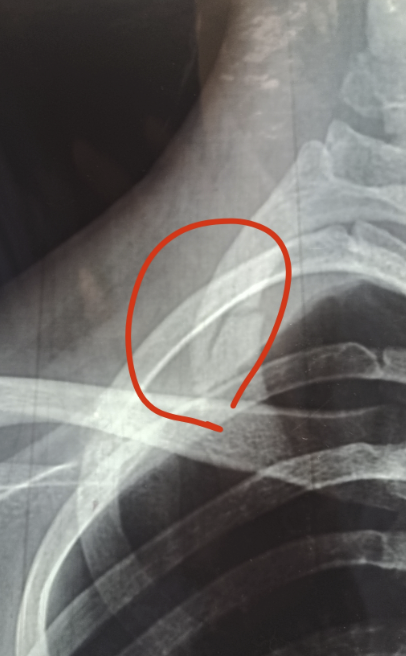

起因是出于艺术行为,被捆着吊了一下午但是并没有感觉到什么异常,只是松绑的时候感觉好像…大概…应该…骨头有点咯噔咯噔的(因为从小身体就不好缺钙,也吃钙片效果甚微)当时并没在意,心想区区一下午我还是有点实力的哼哼。然后当天晚上准备去够衣柜上的箱子,然后!!清脆的听到了骨头嘎嘣一下子,然后就不敢动了…很好,我记得那是一个月明星稀的夜晚,我进了急诊,确诊为锁骨骨折~